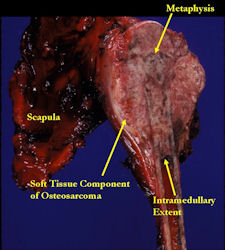

Gross Pathology: Osteosarcoma of Proximal Humerus

- originates from metaphysis of the proximal humerus, extends into surrounding soft tissues

- large soft tissue component that is crossing the glenohumeral joint

- was removed via an extra-articular resection, including scapula (Tikhoff-Linberg resection)